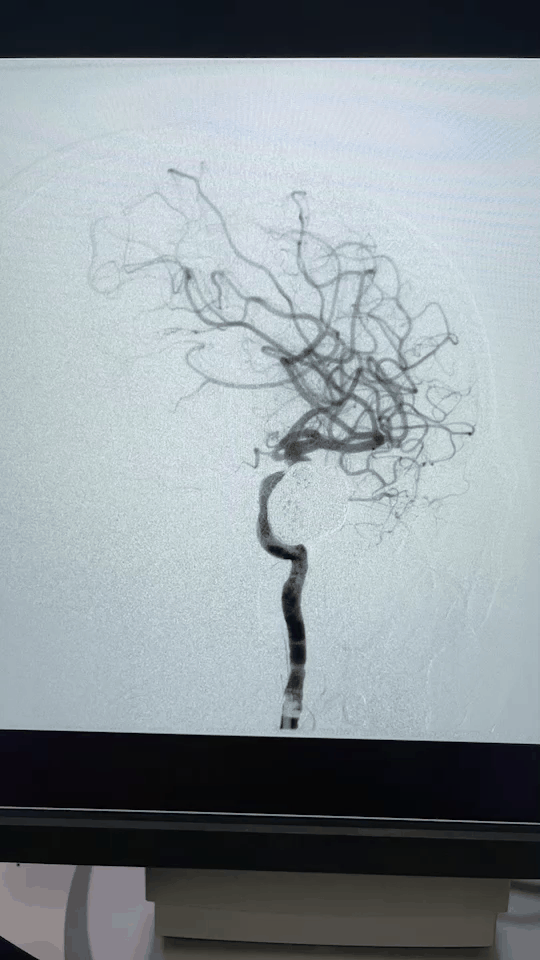

2021年1月18日,杨女士在我院神经外科收治住院,1月20日通过全脑血管造影检查,确诊为左侧颈内动脉海绵窦段巨大动脉瘤。

一个大小约28×26×26毫米的巨大动脉瘤。如葡萄般大小。

经反复沟通,家属选择多支架弹簧圈方案。杨女士于1月26日介入手术治疗。

术中,直径不到1毫米的微导管像走迷宫一样,沿着复杂的血管网络到达脑内,微导管又精确地到达动脉瘤内,填充弹簧圈成功将其栓塞。

2个小时,全神贯注,胆大心细的手术,犹如“刀锋上的芭蕾”,虽然艰难,总算顺利,动脉瘤出血的风险终于解除了。